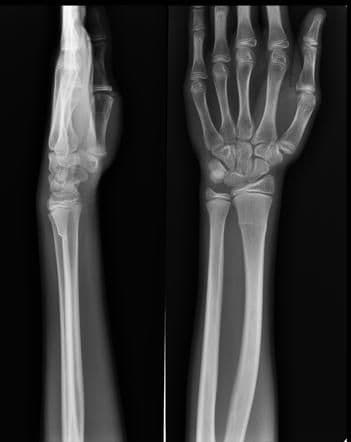

Torus Fracture - यात हाड तुटत नाही पण हाडाचा आकार बदलल्याने वेदना होतात.

Greenstick Fracture - एका बाजूने फ्रॅक्चर, पण हाड वाकल्याने ते पूर्ण न तुटणे. हे फ्रॅक्चर लहान मुलांमध्ये जास्त आढळून येते कारण त्यांची हाडे लवचिक असतात.